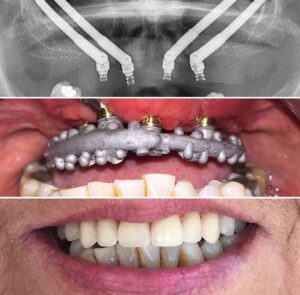

Los implantes cigomáticos son pernos de titanio que se anclan en el hueso cigomático o malar, en lugar de en el hueso maxilar. Se utilizan cuando no es posible colocar implantes dentales tradicionales debido a la falta de hueso en el maxilar.

- Insertar los implantes en el cigoma o hueso del pómulo

- Colocar una prótesis fija provisional fijada a los implantes